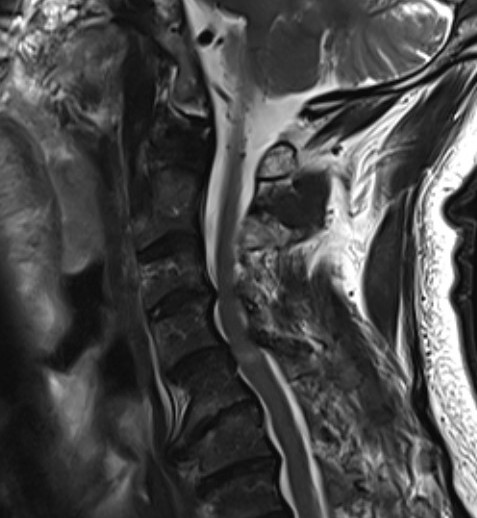

4. Ossification of PLL (OPLL) - more common in certain Asian populations i.e. Japanese

Ossification PLL

CT

Helps distinguish disc from osteophytes

- soft v hard disc

- diagnose OPLL

OPLL on CT

MRI and CT in same patient with OPLL